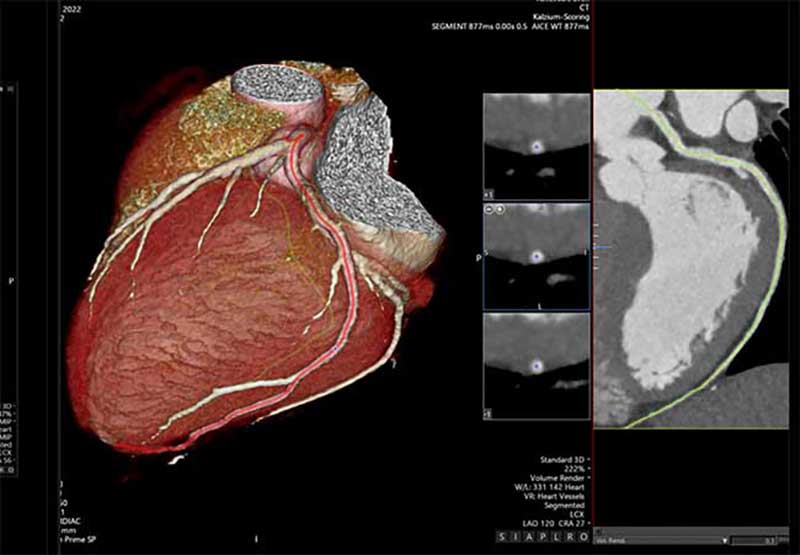

Kardiovaskuläre Radiologie

3D-Darstellung eines Herzens mit Blutgefäßen, CT-Aufnahmen zeigen Details der Herzstruktur.

Die kardiovaskuläre Bildgebung behandelt Erkrankungen des Herzens und der Gefäße. Die 80-Zeilen Computertomographie und 3 Tesla Magnetresonanztomographie ermöglichen hier optimale hochspezialisierte Untersuchungsmöglichkeiten. Die Patientenauswahl und Indikationsstellung erfolgt interdisziplinär, u.a. mit der Kardiologie und Angiologie, ebenso jedoch mit den operativen Fächern Plastische Chirurgie, Unfallchirurgie, Allgemeinchirurgie und Urologie.

Aufgrund der kurzen Untersuchungszeiten setzen wir die CT bevorzugt bei dringlichen Fragestellungen ein. Sie ist unter anderem Goldstandard für die Untersuchung von Lungenarterienembolien. Wir nutzen sie, um minimalinvasive Verfahren zu indizieren und zu planen. Verletzungen großer Gefäße, wie der Hauptschlagader, sind eine zentrale Domäne der CT Erstliniendiagnostik.

Ist eine sehr hohe Genauigkeit bzw. Ortsauflösung erforderlich, um diagnostische Aussagen zu kleinen peripheren Gefäßabschnitten zu geben, nutzen wir CT für die anatomische Feindarstellung im hochauflösenden 0,5 mm-Bereich und die MRT oft zur Erfassung funktioneller Zusatzinformationen, wie Perfusions-, oder Diffusionspathologien. Die Ergebnisse spielen oft eine entscheidende Rolle bei Therapieplanungen. So können Untersuchungen vor der minimalinvasiven Implantation von Aortenprothesen bzw. zusätzliche Therapieplanungen nach erfolgter Behandlung großer Aneurysmen äußerst genau und Patienten-schonend durchgeführt werden. Sie liefern der Operateurin bzw. dem Operateur essenzielle Informationen für spätere Eingriffe. Auf die gesamte diagnostische Information können wir während minimal-invasiver operativer Eingriffe vor Ort zugreifen.

Ein weiterer Schwerpunkt ist die computertomografische Untersuchung der Herzkranzgefäße. Dabei messen wir zunächst die vorhandenen Kalkablagerungen, vergleichen die gemessenen Werte mit Durchschnittswerten und bestimmen das individuelle Herzinfarktrisiko. In den meisten Fällen ersparen wir den Patientinnen und Patienten eine invasive Herzkatheteruntersuchung. Anschließend stellen wir mit der nichtinvasiven CT-Angiographie die Herzkranzgefäße direkt dar. Damit legen wir fest, ob eine invasive Herzkatheteruntersuchung durchführt werden muss. Indikation und Interpretation der Untersuchung erfolgt daher in enger Zusammenarbeit mit der Kardiologie in entsprechenden Konferenzen. Unsere international standardisierte Dokumentation, die mit der aktuellen Praxis in Herzkatheterlaboren kompatibel ist, schafft eine strukturierte Befundung. Dieses Vorgehen ermöglicht eine schnelle und exakte interdisziplinäre Kommunikation der Untersuchungsergebnisse.